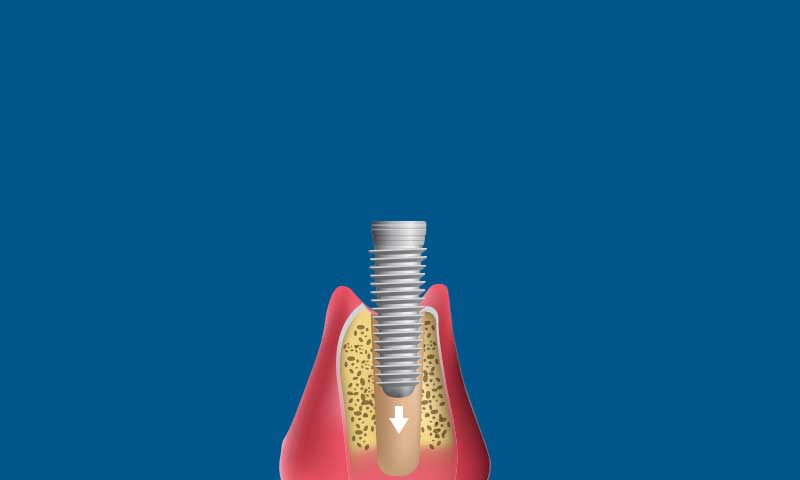

Dental Implant Surgery.

Your dentist at Heathrow Dentistry then places a titanium screw, also known as the implant body, into your jawbone. We can use dental sedation to help put you at ease during this short surgery.

Osseointegration. We close the gum incision and leave the implant to heal for three months. During this period, the surrounding bone grows over the implant to fuse with it. This process creates a sturdy platform to support the prosthetic tooth.